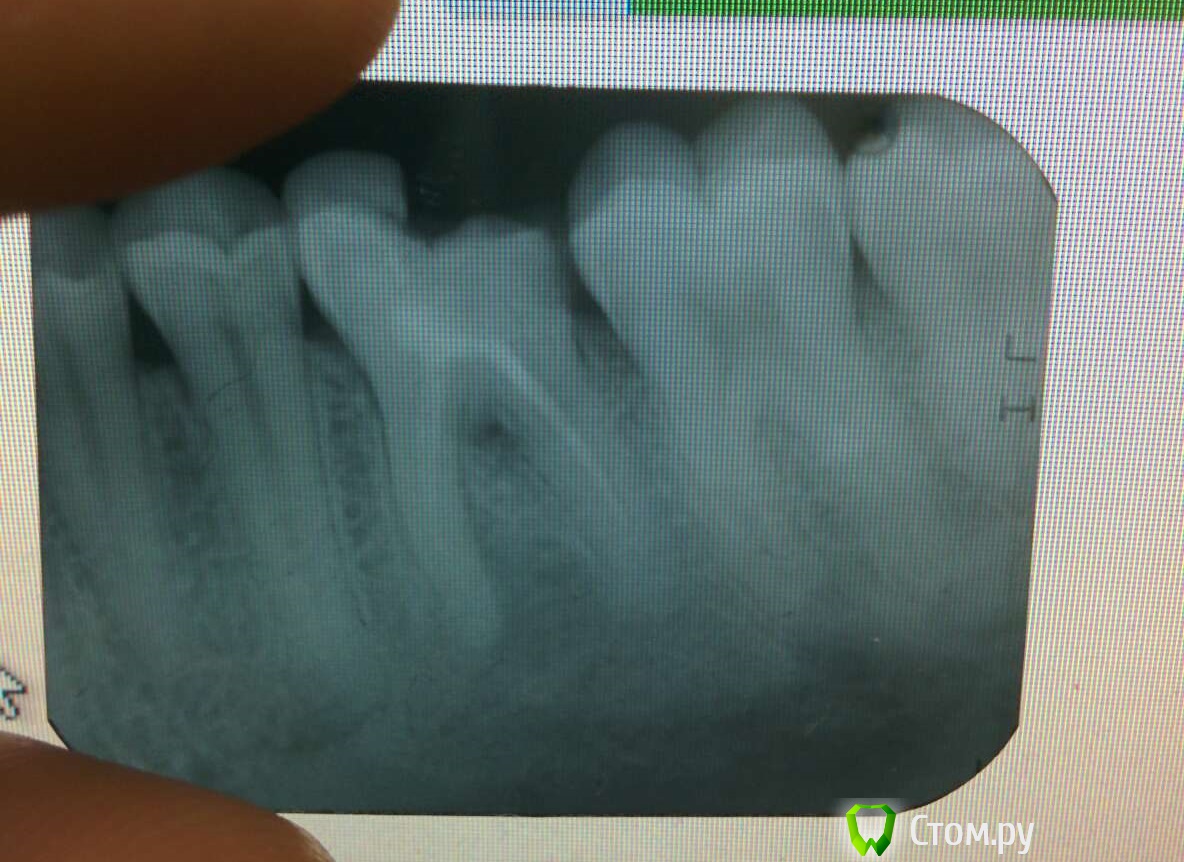

clock Опубликовано 1 октября, 2014 Поделиться Опубликовано 1 октября, 2014 Доброго времени суток! На днях на десне с внутренней стороны появилось вздутие. Боли не было, тем не менее на следующий день записался к дантисту. Сделали рентген, хирург сказал: "Надо рвать!" Хоть он и утверждал безапелляционно, но я не дался. Зуб лет пять назад пломбировали. Собственно, очень рассчитываю на совет: есть ли шанс сохранить зуб, или действительно надо удалять? Ссылка на комментарий

red_butler Опубликовано 1 октября, 2014 Поделиться Опубликовано 1 октября, 2014 если вести речь, видя только данный снимок, то побороться за зуб можно. Только Вы должны понимать, что лечение зуба с последующим протезирование будет как минимум сравнимо, если не дороже, варианта с удалением и имплантацией. 3 Ссылка на комментарий